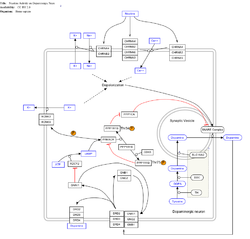

imgi_164_250px-NicotineDopaminergic_WP1602.png